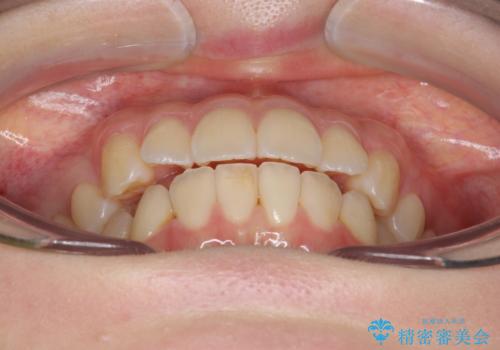

下の八重歯 歯を抜かずに インビザライン治療

- 歯並びのがたつきを主訴に来院。

抜歯してワイヤー矯正という選択肢も提案しましたが、マウスピース矯正で、歯を抜かずに並べてほしいとのことでした。

スペースを確保するために、歯をわずかに削る処置、奥歯を後ろに下げる処置(インプラント矯正)を行っています。

途中患者様のご都合で治療を中断していたため、長くかかっていますが、実質2年程度で終わる内容でした。